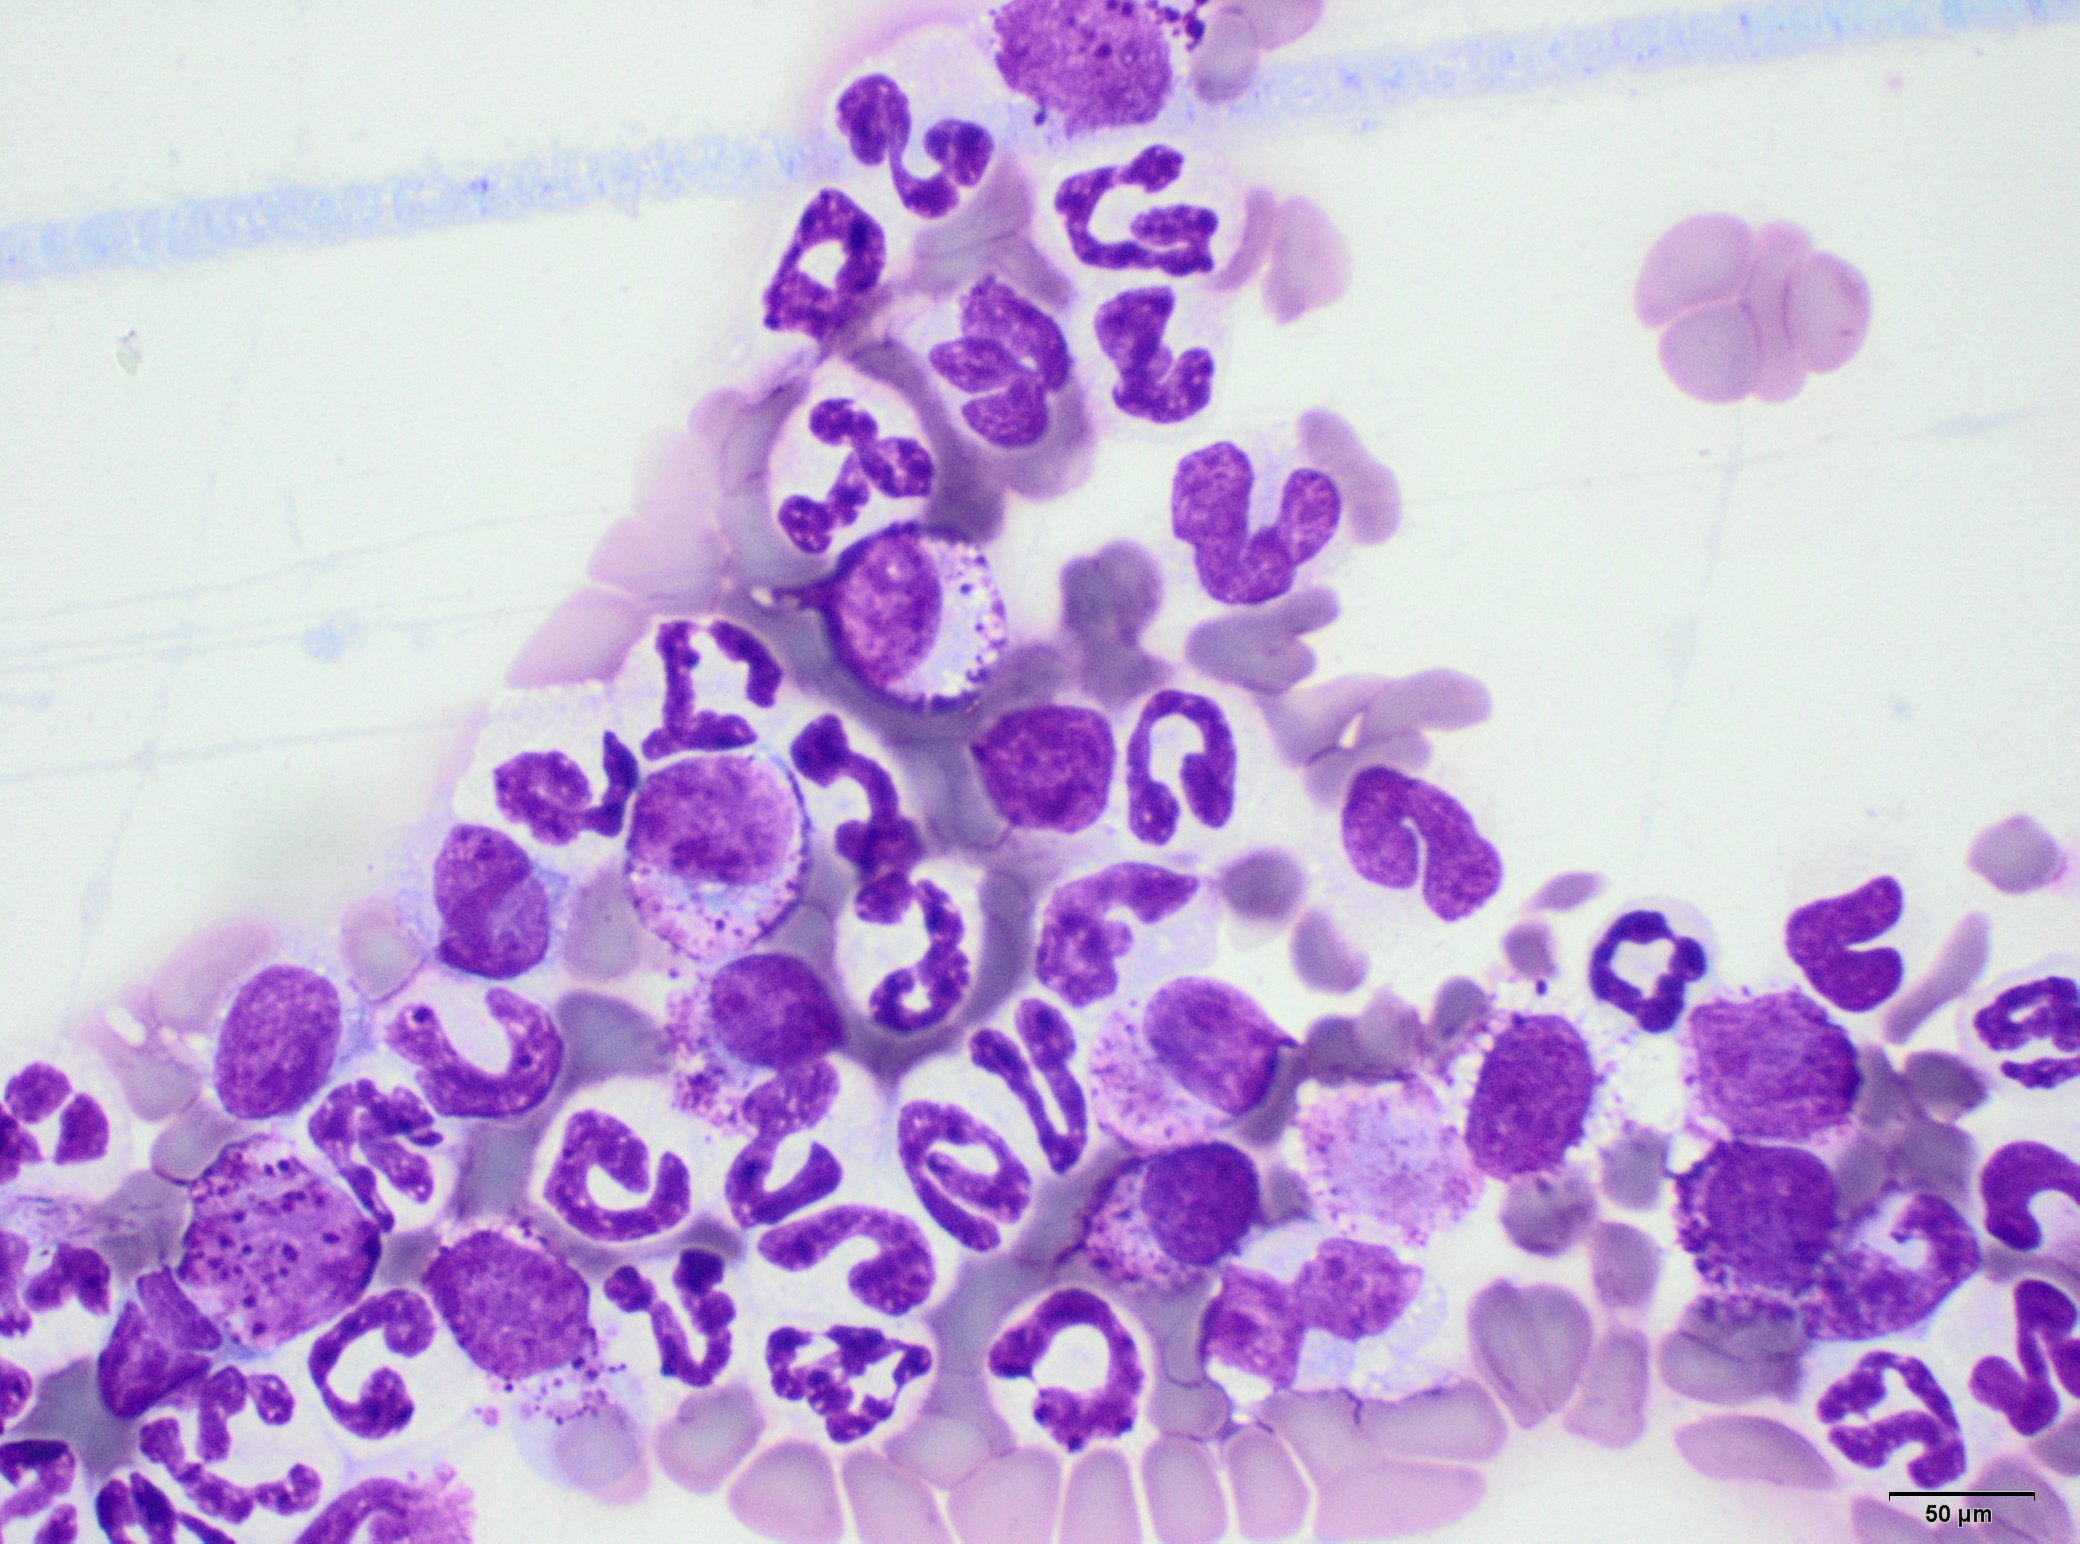

10) Mastocytémie (présence de mastocytes dans le sang) n’est pas synonyme de tumeur mastocytaire. C’est particulièrement vrai chez le chien chez qui plus de 50% des mastocytémies ne sont PAS liées à la présence d’un néoplasme mastocytaire. Néanmoins, en cas de mastocytémie, surtout si elle est massive comme dans le cas ci-dessous, la recherche d'une tumeur mastocytaire reste indiquée.